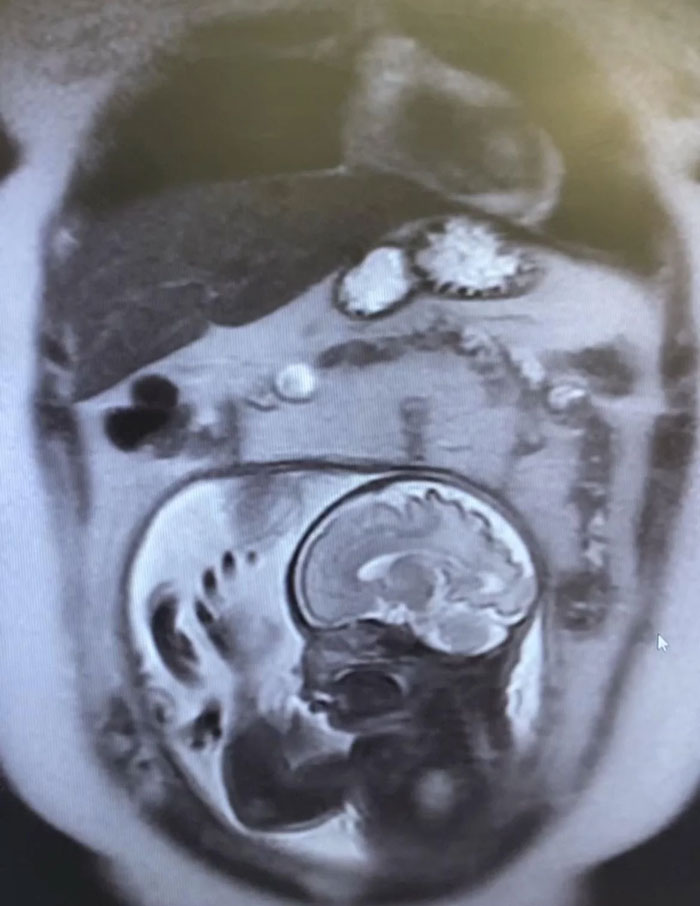

An MRI View You Won’t See Every Day